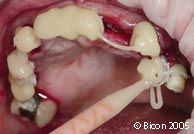

带着愈合帽就位的种植体。 |

![]() |